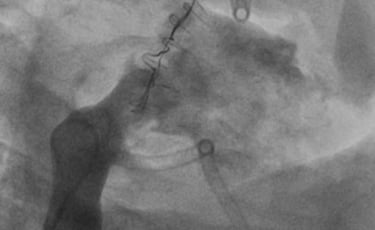

The tech has been developed through 3 years of testing and iterations based on test data and user input including bench at Resolution Medical, beating heart model at Lifetec Group and successful In-vivo deployment in an animal modal at the pre-clinical reference lab at IMMR/Veranex in Paris with extremely encouraging results.